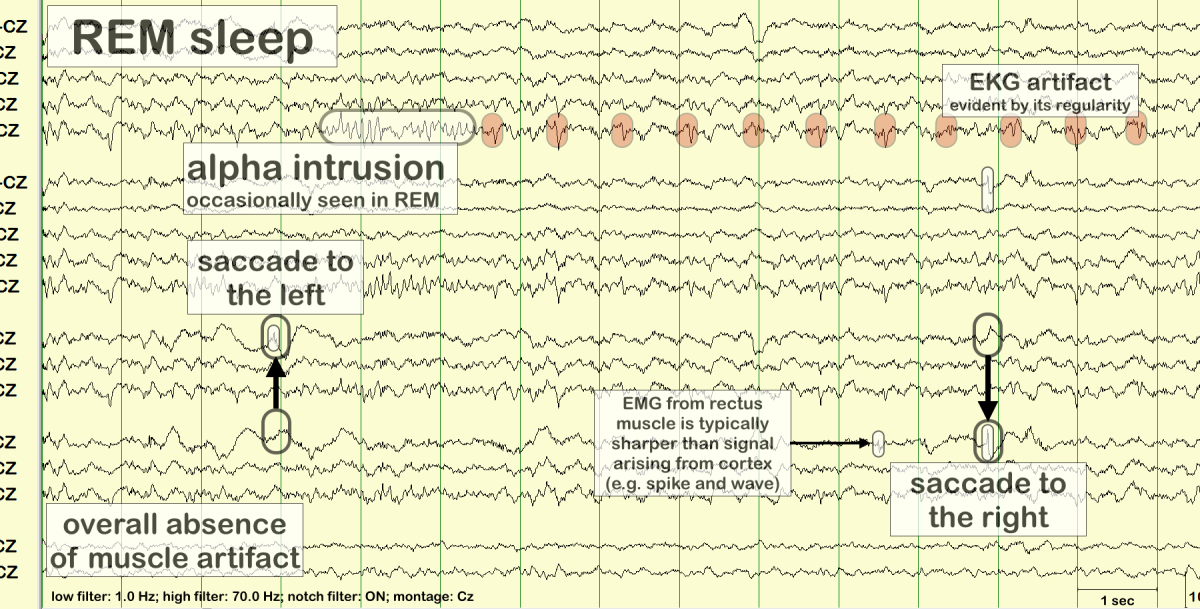

REM (Rapid Eye Movement) sleep is a crucial phase of the sleep cycle, characterized by rapid movements of the eyes, increased brain activity, and vivid dreaming. It accounts for approximately 20-25% of an adult’s sleep time and plays a vital role in cognitive functions such as memory consolidation, emotional regulation, and creativity. Understanding the physiological processes that occur during REM sleep can enhance our appreciation of its importance.

During REM sleep, several physiological changes take place. The brain exhibits heightened activity akin to wakefulness, which can be observed through brain wave patterns. This phase is marked by increased heart rate, irregular breathing, and the temporary paralysis of major muscle groups, preventing the sleeper from acting out dreams. The body experiences a drop in core temperature and changes in hormonal levels, including surges in neurotransmitters like acetylcholine, which promote dreaming. REM sleep typically occurs after about 90 minutes of sleep and recurs multiple times throughout the night, lasting longer with each successive cycle.

In contrast, REM sleep is marked by increased brain activity, rapid eye movements, and vivid dreaming. This stage is essential for cognitive functions such as memory consolidation, problem-solving, and emotional regulation, which differentiates it significantly from the restorative processes occurring during non-REM sleep stages.